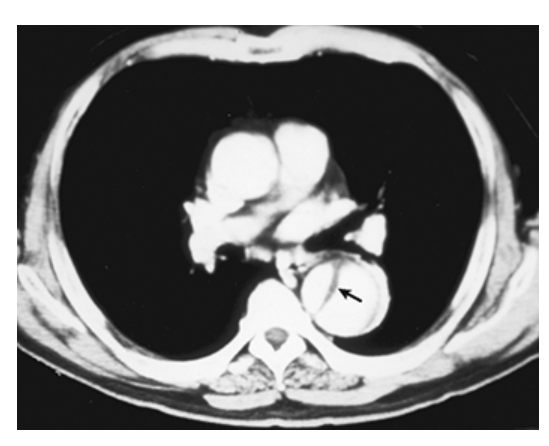

Type B Dissecting Aneurysm. Axial CT with IV contrast shows a Type B dissecting aneurysm involving the descending thoracic aorta with two lumens (true and false) separated by an intimal flap.